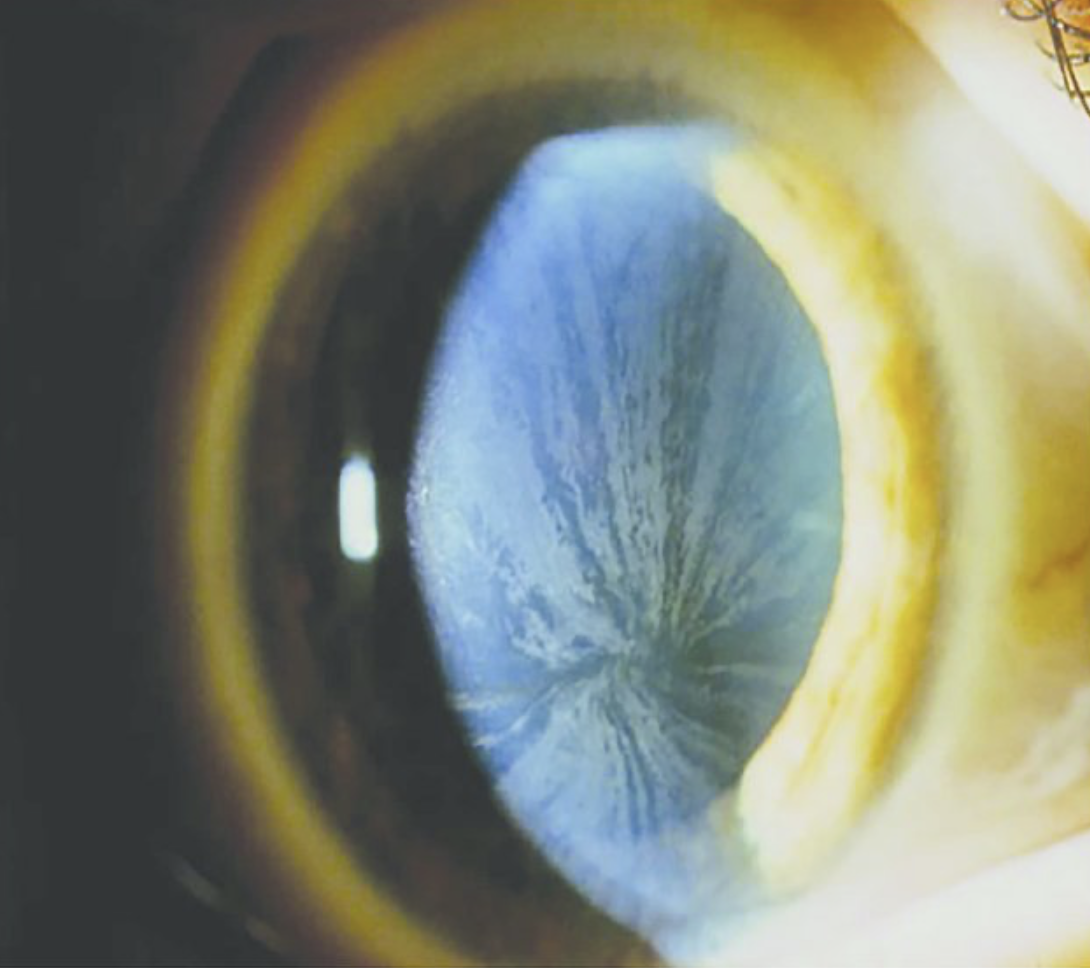

Die Multiorganerkrankung Morbus Fabry kann sich ebenso durch ihr ganz besonderes Erscheinungsbild am Auge bemerkbar machen:

⚠: Cornea verticillata im Bereich der Hornhaut junger Patienten. Die Hornhautablagerungen scheinen sich von einem zentralen Punkt aus gesehen speichenradförmig inferior der Pupille nach außen zu drehen.

Abbildung 2: Cornea verticillata Grad III bei Morbus Fabry3

Eine wichtige Differentialdiagnose ist die medikamentöse Einnahme von Amiodaron, Chloroquin, Hydroxychloroquin, Indomethacin oder auch Phenothiazin. Diese Medikamente können ebenso zu einer Cornea verticillata führen.4